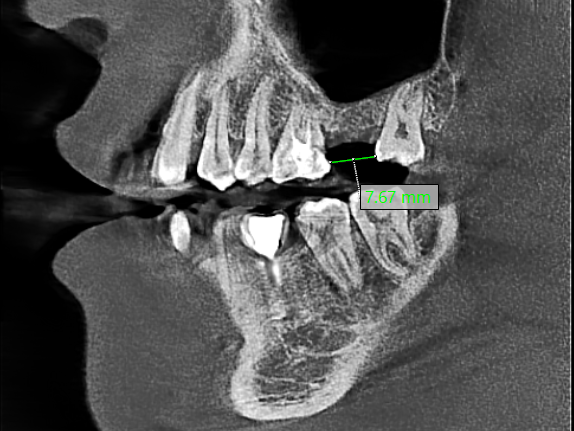

经口腔科种植专家术前详细检查、评估后,决定不采用传统的上颌窦底外提升术,而选择上颌窦底水冲式内提升技术,这种手术对软硬组织的创伤极小,出血量少,微创入路,帮助王大叔成功增加了约 7 mm 的骨高度。

完成上颌窦底提升后,庄根鹰团队为其植入了一枚 8 mm 的种植体,能够满足老王正常的牙齿咀嚼功能。

术前:缺牙区牙槽骨高度严重不足

术后即刻:缺牙区牙槽骨高度提升明显,植体三维位置理想